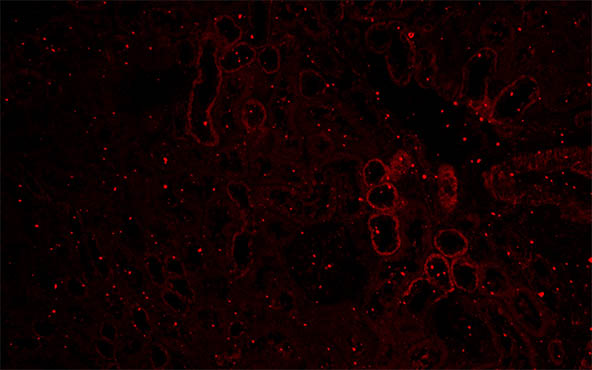

病理医生需要制备待检查的样本玻片,以满足医院和诊所中诊治患者的医生的要求。近日,深圳某生物公司需要一套荧光显微镜,以用于病理玻片和荧光玻片观察,明美工程师推荐科研级荧光显微镜MF43-N,搭配2000万像素显微镜相机MDX10。

荧光显微镜MF43-N配备6孔落射荧光模块和超长寿命LED荧光光源,可扩展升级实现明场、暗场、相差、荧光观察,高数值孔径半复消色差物镜,分辨率高,成像清晰无色差畸变。